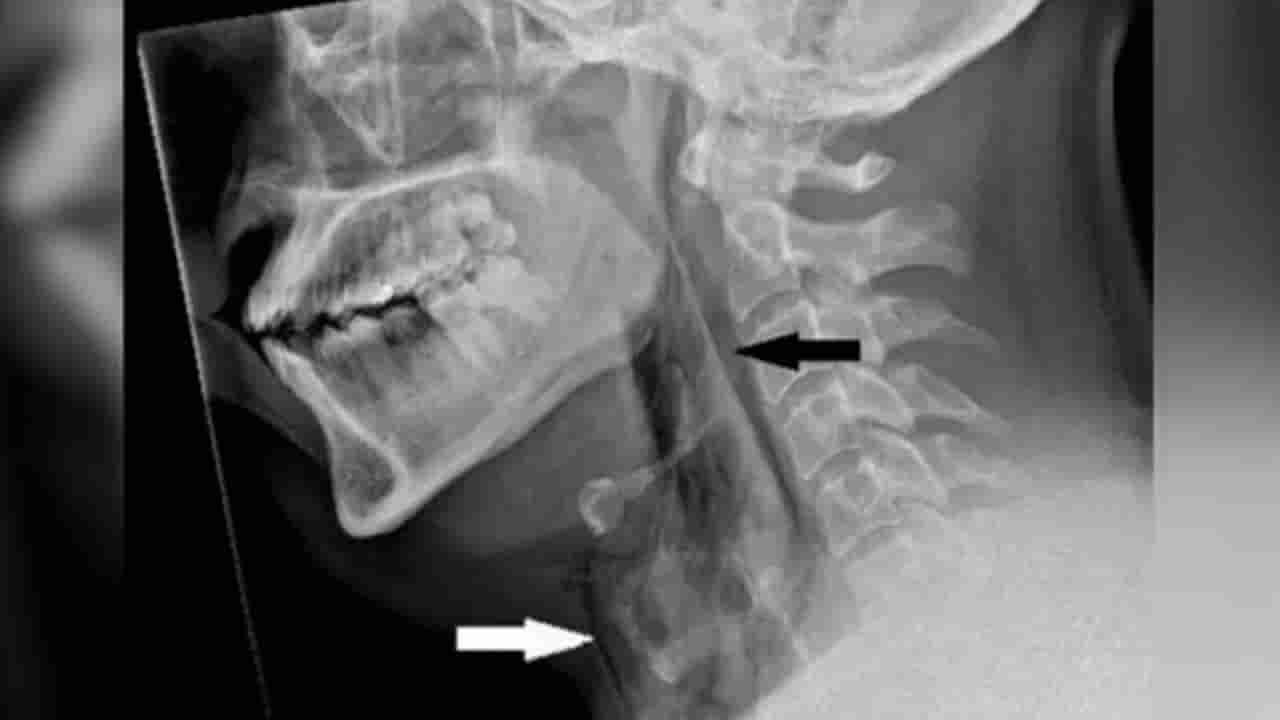

ఆ తర్వాత అతనికి మెడ నొప్పి, వాపు వచ్చాయి. మెడ కదలడం కష్టమైపోయింది. దీంతో అతను ఆస్పత్రికి వెళ్లగా.. టెస్టులు చేసిన డాక్టర్లు గొంతులో చిన్న చిల్లు ఉండటాన్ని గుర్తించారు. తుమ్మినప్పుడు… ముక్కు నొక్కి, నోరు మూసుకుని ఆపడం వల్ల.. గొంతులో గాలి చాలా బలంగా నిలిచిపోయింది. ఇది గొంతు లోపల ఒత్తిడి పెంచి పగిలిపోయేలా చేసింది. ఆ వ్యక్తికి శస్త్రచికిత్స అవసరం లేకుండా, కొన్ని రోజులు ఆసుపత్రిలో ఉంచి గమనించారు. రెండు వారాలు శ్రమకు దూరంగా ఉండాలని చెప్పారు. ఐదు వారాల తర్వాత అతని గొంతు పూర్తిగా మామూలు అయ్యింది.